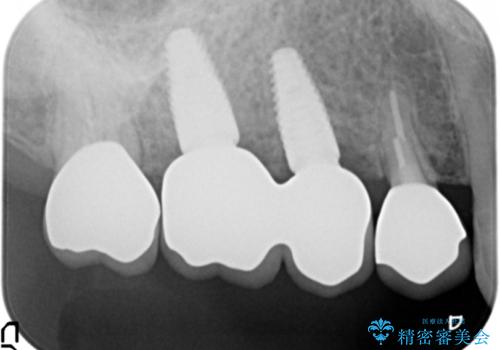

- 125.4万円(インプラント×2・チタンカスタムアバットメント×2・ジルコニアクラウン×4・仮歯×4)費用は治療当時の料金となります

インプラント治療が終了し、しっかりと咬合機能が回復しまた食事が楽しめるようになりました。